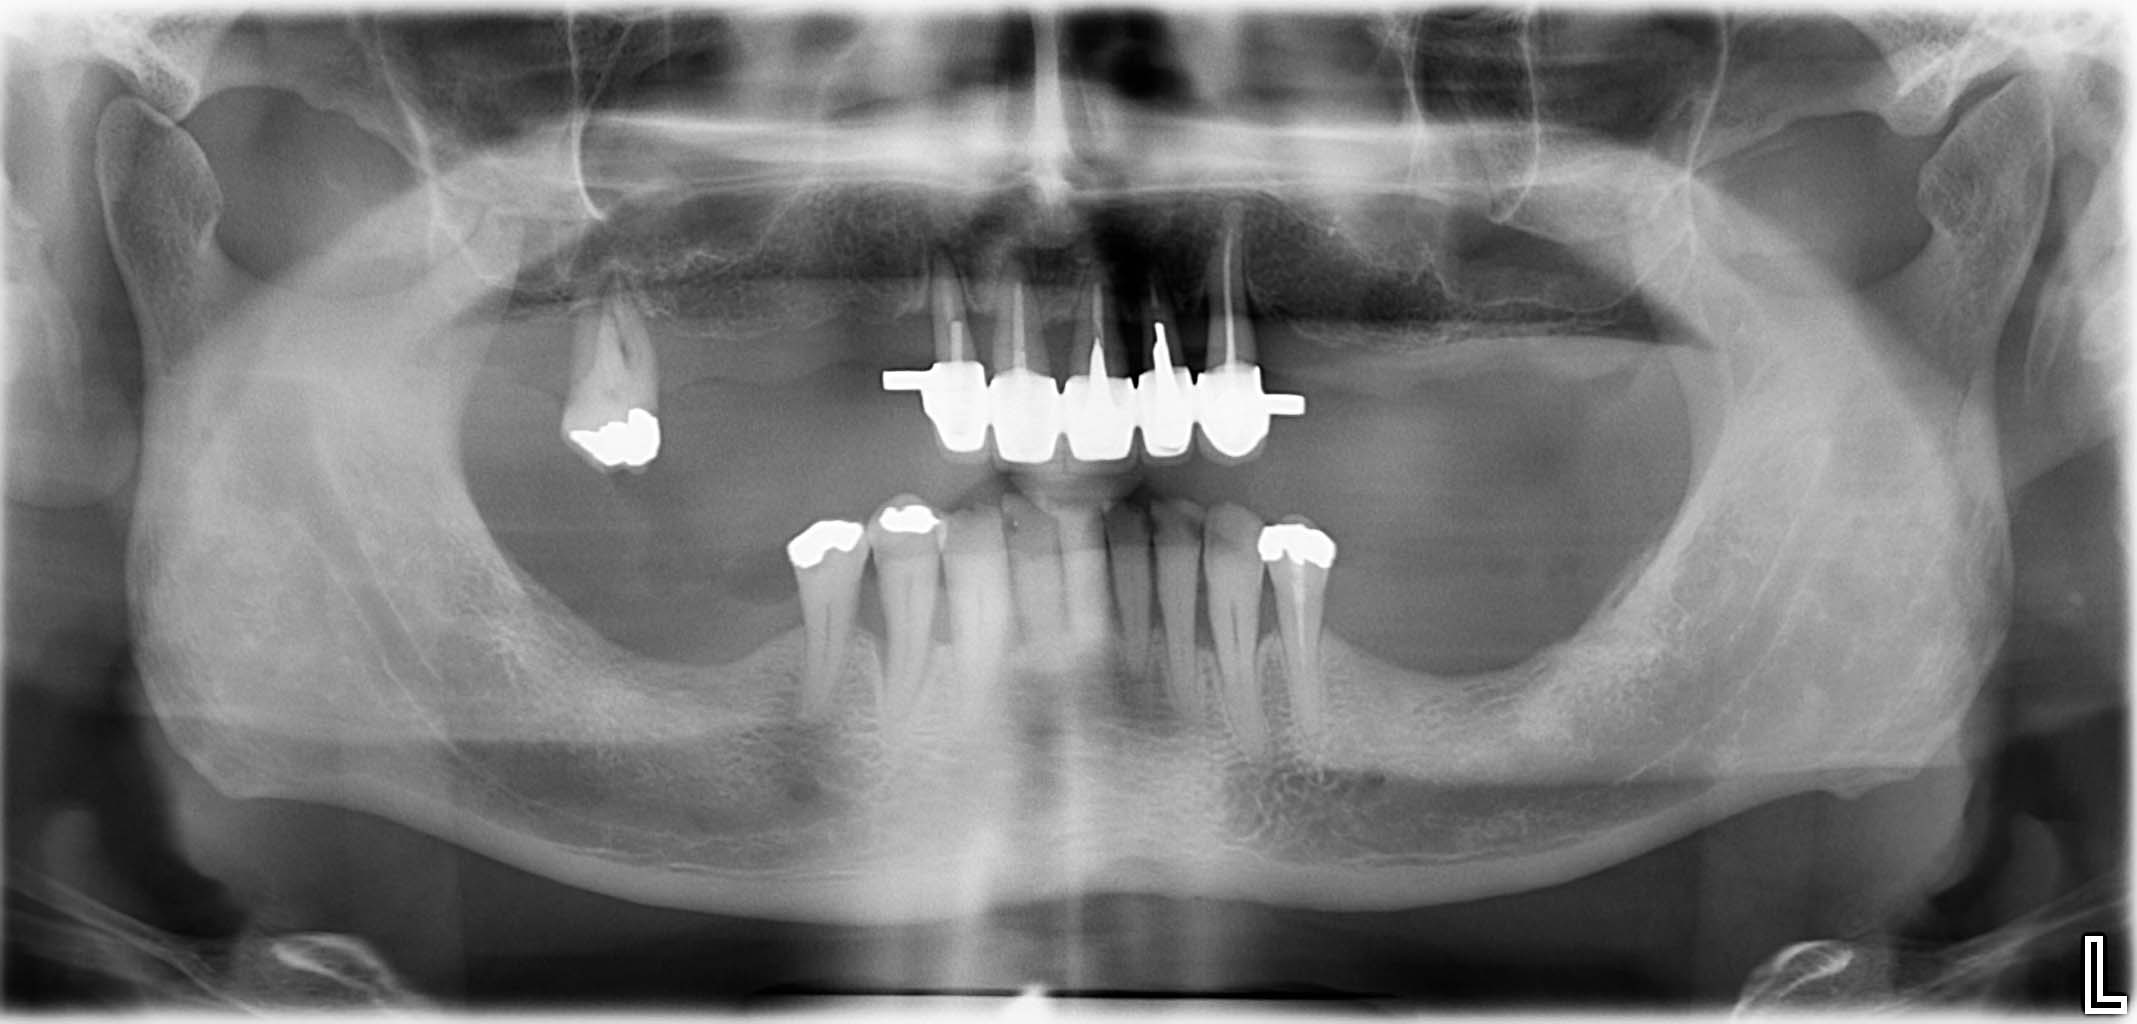

Ausgangssituation: Zahn 36 mit apikaler Beherdung, nicht erhaltungswürdig